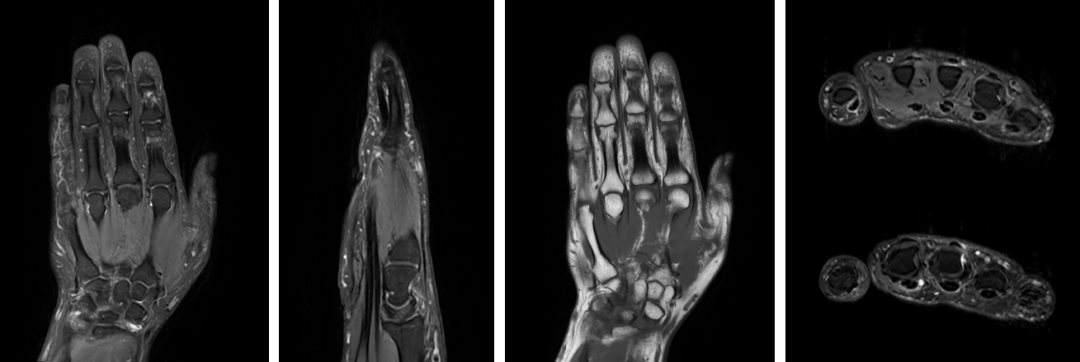

适用范围超广泛,这些情况都能查

GE3.0TMRI的适用范围覆盖全身多个部位,为各类疾病诊断提供精准依据,核心检查方向包括:

3.0T高场强带来的极致成像效果,能清晰显示神经系统、体部脏器、骨关节、心血管等部位的细微病变,无论是早期脑梗塞、微小脑肿瘤,还是肝癌、胰腺癌等恶性肿瘤的早期筛查,亦或是肩袖撕裂、半月板损伤等软组织损伤,都能精准捕捉,让病灶无处隐藏。